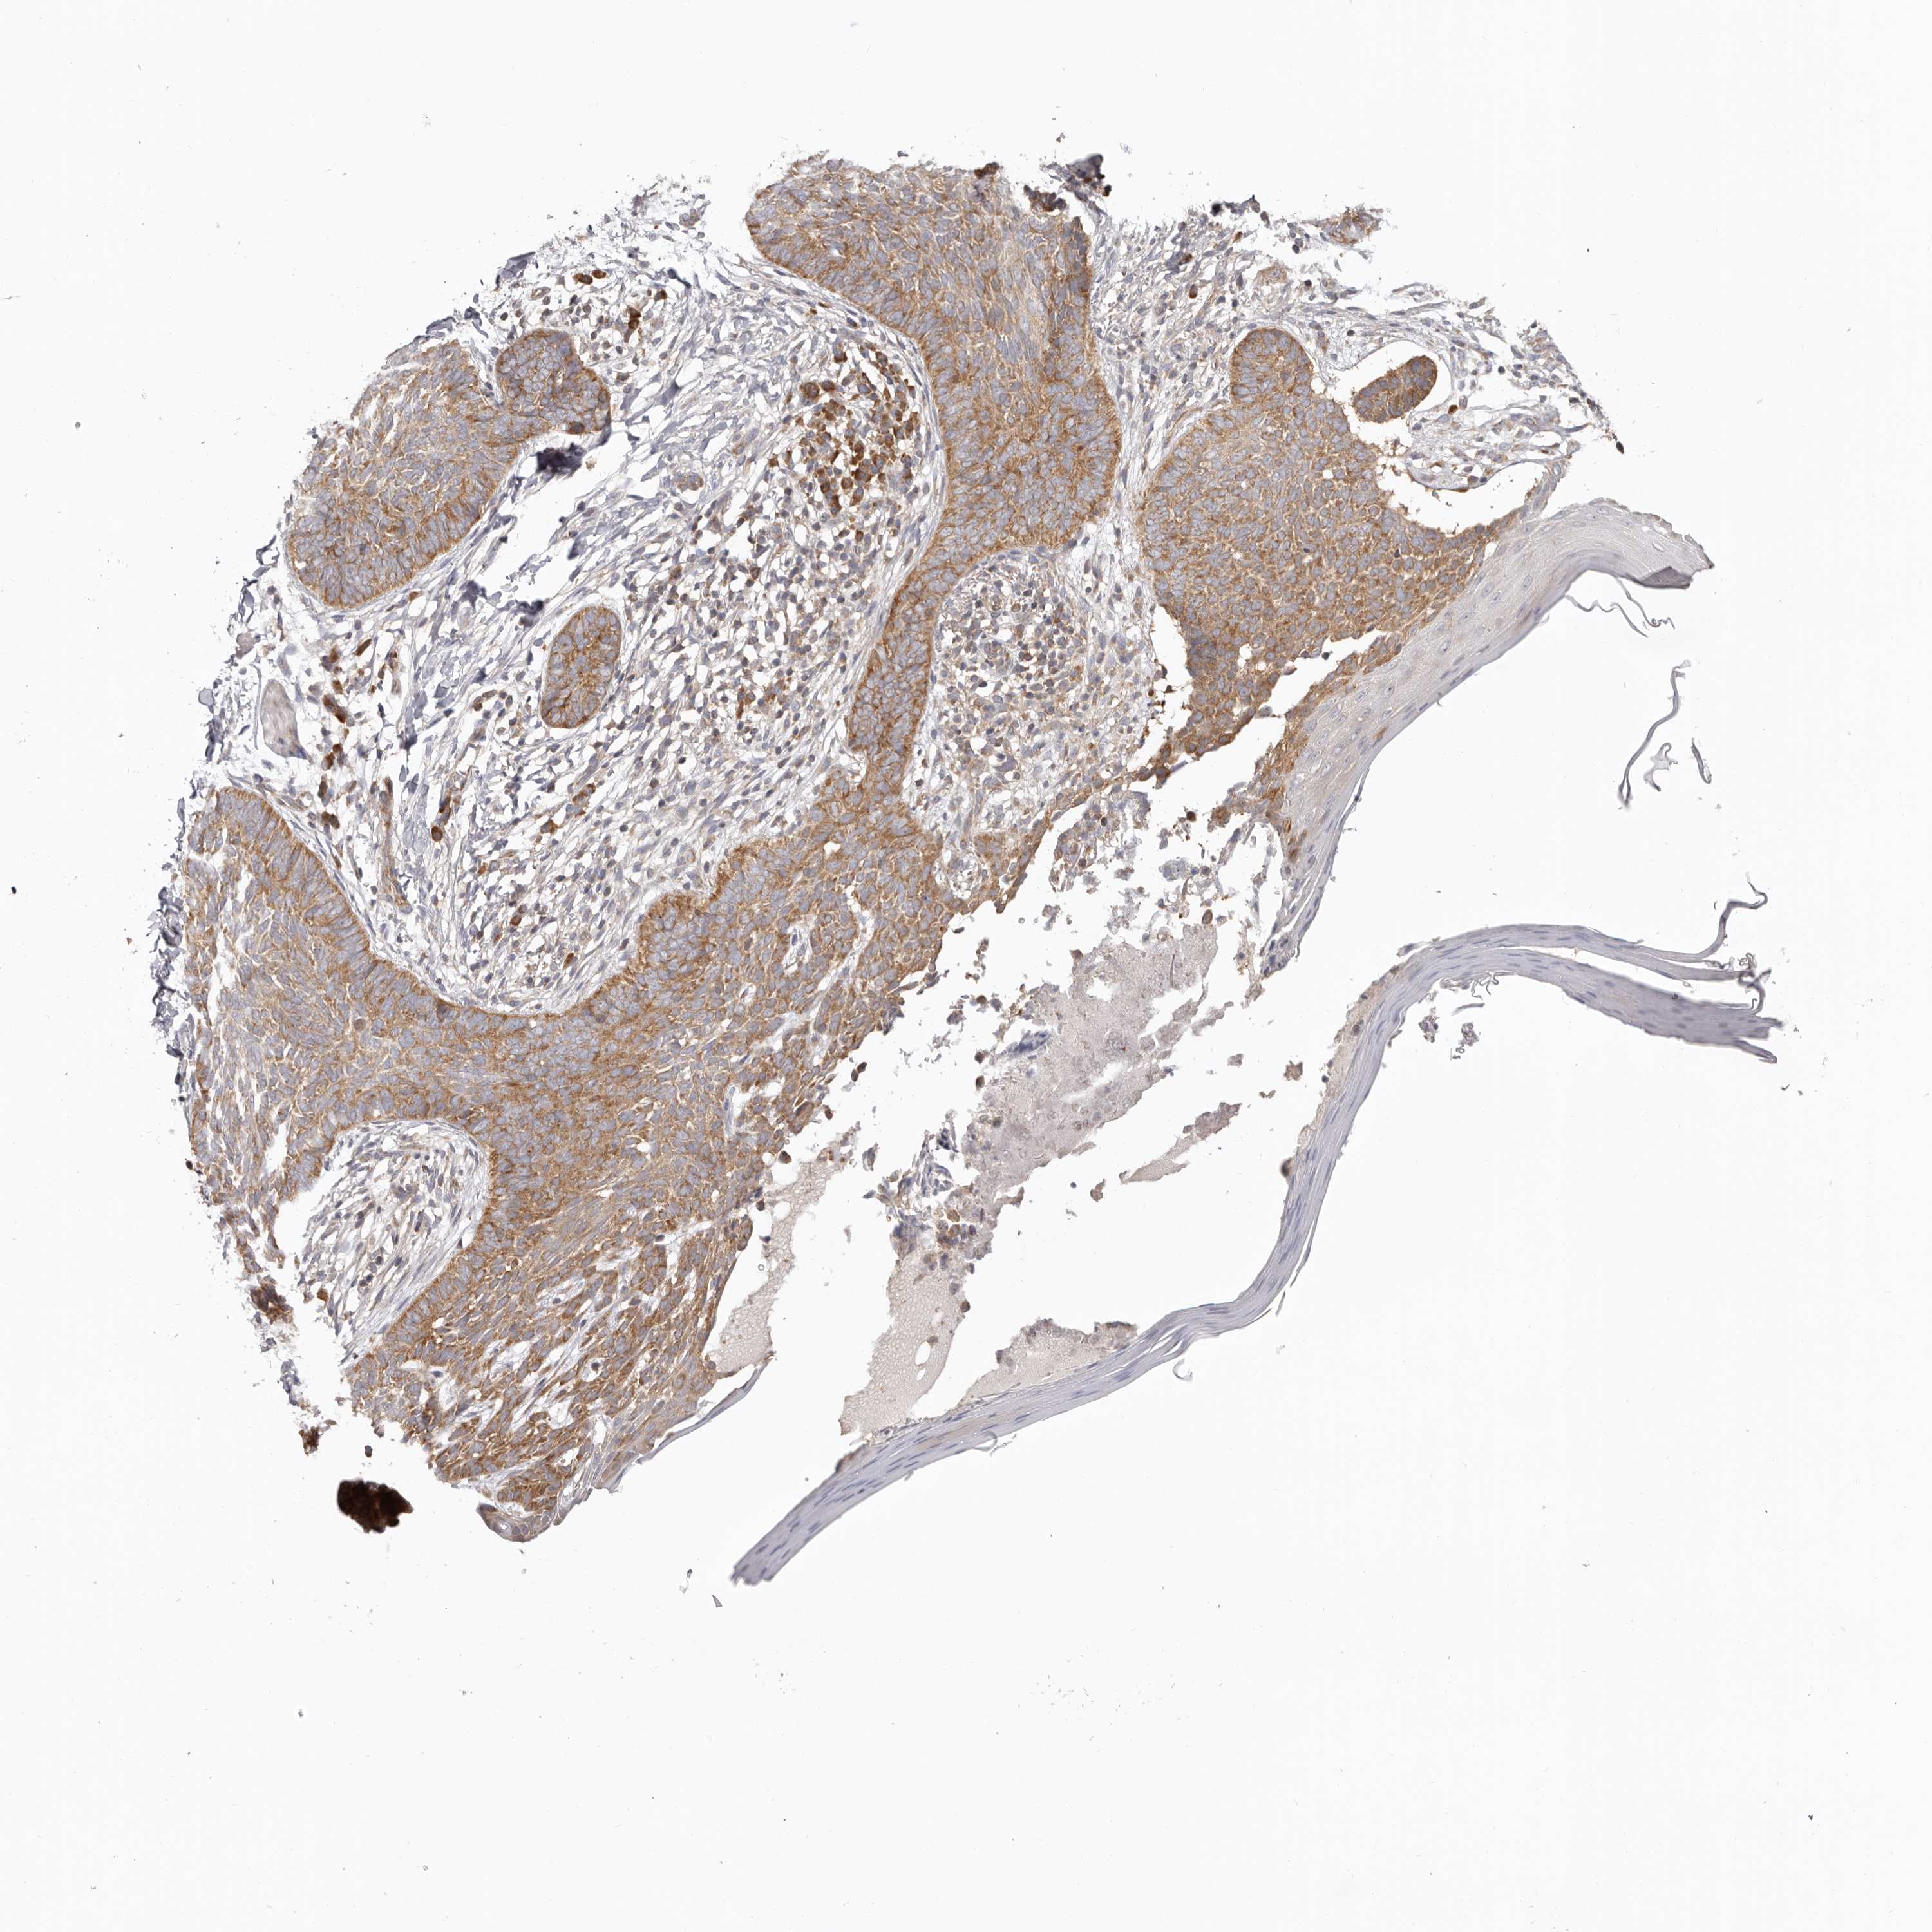

SKIN CANCER - Protein expressioni

A mouse-over function shows sample information and annotation data. Click on an image to view it in a full screen mode. Samples can be filtered based on level of antibody staining by selecting one or several of the following categories: high, medium, low and not detected. The assay and annotation is described here.

Antibody staining in the annotated cell types in the current human tissue is reported as not detected, low, medium, or high, based on conventional immunohistochemistry profiling in selected tissues. This score is based on the combination of the staining intensity and fraction of stained cells.

Each image is clickable and will lead to virtual microscopy that enables deeper exploration of all samples and also displays staining intensity scores, fraction scores and subcellular localization as well as patient and tissue information for each sample.

Antibody HPA027901

Staining

High

Intensity

Strong

Location

Nuclear

Cytoplasmic/membranous

Cytoplasmic/membranous,nuclear

Basal cell carcinoma

Squamous cell carcinoma, NOS

Squamous cell carcinoma, metastatic, NOS